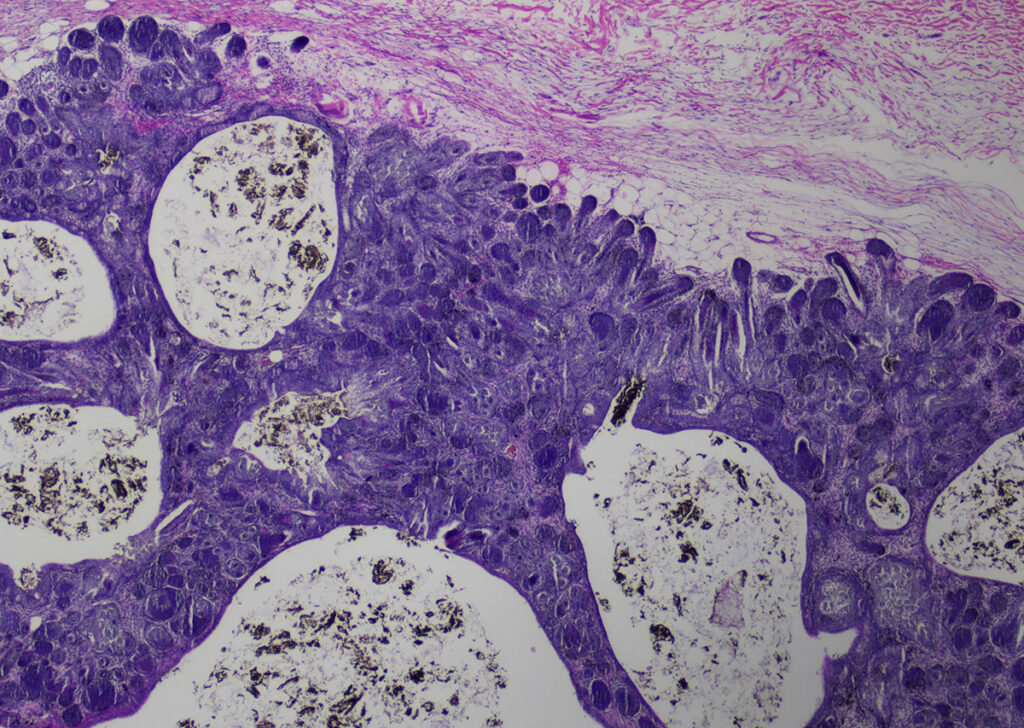

Abb. 5: Trichofollikulom (HE-Färbung, 20fache Vergrößerung)

Bildquelle: Laboklin

Insgesamt wurden 157 epitheliale Tumoren eingesandt. Davon waren 142 gutartig und 15 bösartig. Es wurden 124 Trichofollikulome (Abb. 5), 5 Trichoepitheliome, 3 Pilomatrixome, 3 Adenome und 7 sonstige benigne Neoplasien diagnostiziert. Ferner wurden 5 Adenokarzinome, 5 nicht näher bestimmbare Karzinome, 3 Plattenepithelkarzinome und 2 Talgdrüsenkarzinome beschrieben.

In der vorliegenden Studie über spontane Tumoren beim Meerschweinchen dominierten die gutartigen Neoplasien der (Unter-)Haut. Das Lipom ist der weitaus häufigste Tumor, gefolgt vom Trichofollikulom.